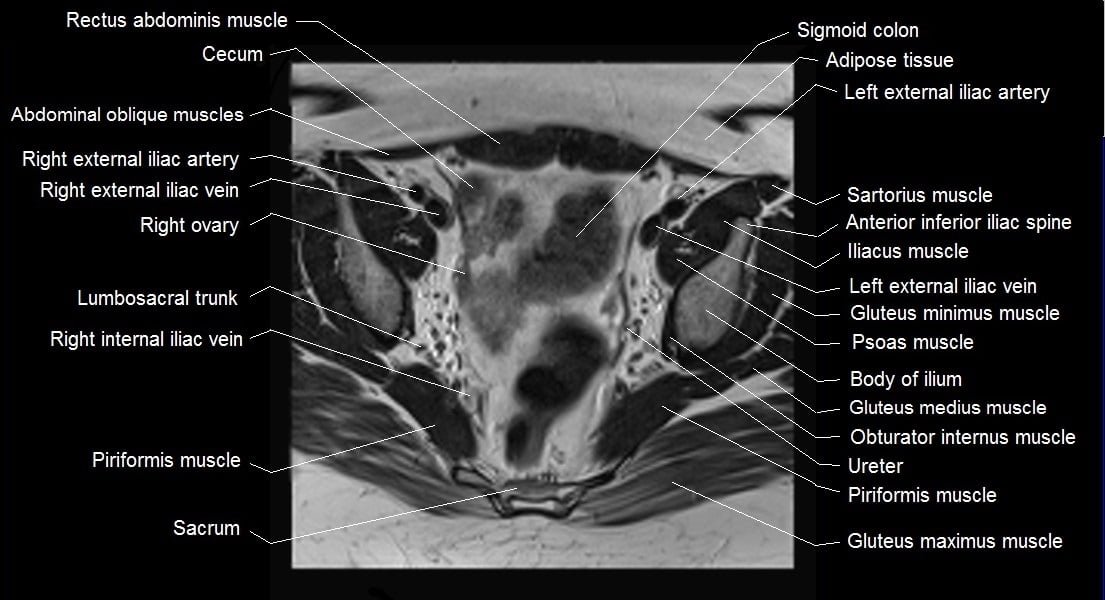

MRI Axial Cross-Sectional Anatomy of Female Pelvis

mri female pelvis anatomy axial